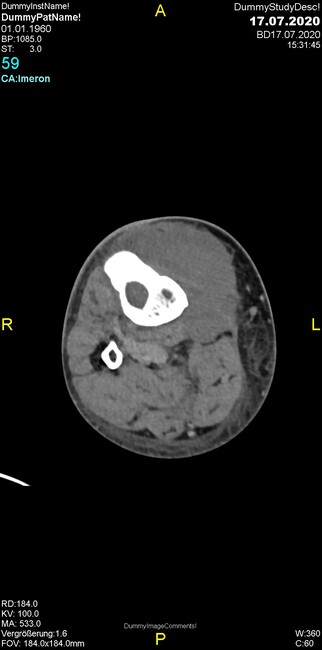

Um welche Modalitäten handelt es sich?

- Röntgen p.a. und lateral, CT coronar Knochenfenster, CT axial Weichgewebsfenster

Was fällt in der Projektionsradiographie auf?

Was fällt in der CT im Knochenfenster auf?

- Osteolyse der Tibiametaphyse unter Beteiligung der Kortikalis

Was kommt differentialdiagnostisch in Frage?

- Osteomyelitis mit Weichgewebsanteil

- Metastase mit pathologischer Fraktur